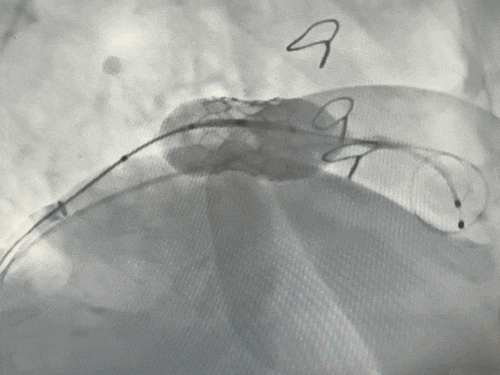

释放瓣膜

术后复查左室造影:二尖瓣反流完全消失,瓣膜功能良好,且成功避免了左室流出道梗阻等严重并发症

将25#球囊扩张式瓣膜输送系统沿加硬导丝送至二尖瓣环位置。在TEE及DSA多角度共同确认下,精确定位。在RVP下,快速充盈球囊,将新瓣膜成功释放并固定于原生物瓣环内。即刻TEE及造影评估显示:人工瓣膜位置良好,功能正常,未见瓣周漏,左室流出道通畅。